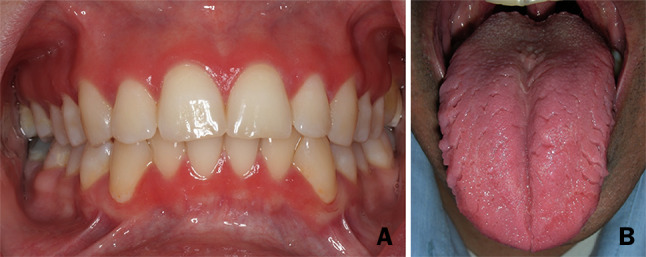

We have retrieved a total of 13 patients (six females and seven males; aged 11 to 56 years at diagnosis) who fulfilled the above criteria. The patient characteristics and their clinical features, including intra- and extra-oral manifestations, are presented in Table 1 and in Figs. 1, 2 and 3. All patients presented with a remarkable, well-demarcated symmetrical fiery-red erythema on the palatal mucosa, especially in the pre-maxilla (area of the rugae) (Fig. 1). Focal fiery-red hyperplastic gingivae in the upper jaw were recorded in 3 patients (#7, #8 and #13; Fig. 2a). Fissured tongue was noticed in 6 cases (#2, #3, #4, #5, #8 and #13; Fig. 2b), and geographic tongue in 4 patients (#2, #3, #5 and #11; Fig. 2b). Involvement of the lip commissure, presenting as angular cheilitis, was seen in patient #8.

Fig. 2.

Oral (non-palatal) lesions/conditions. a Gingival involvement in patient #13. b Tongue involvement: geographic and fissured tongue in patient #3